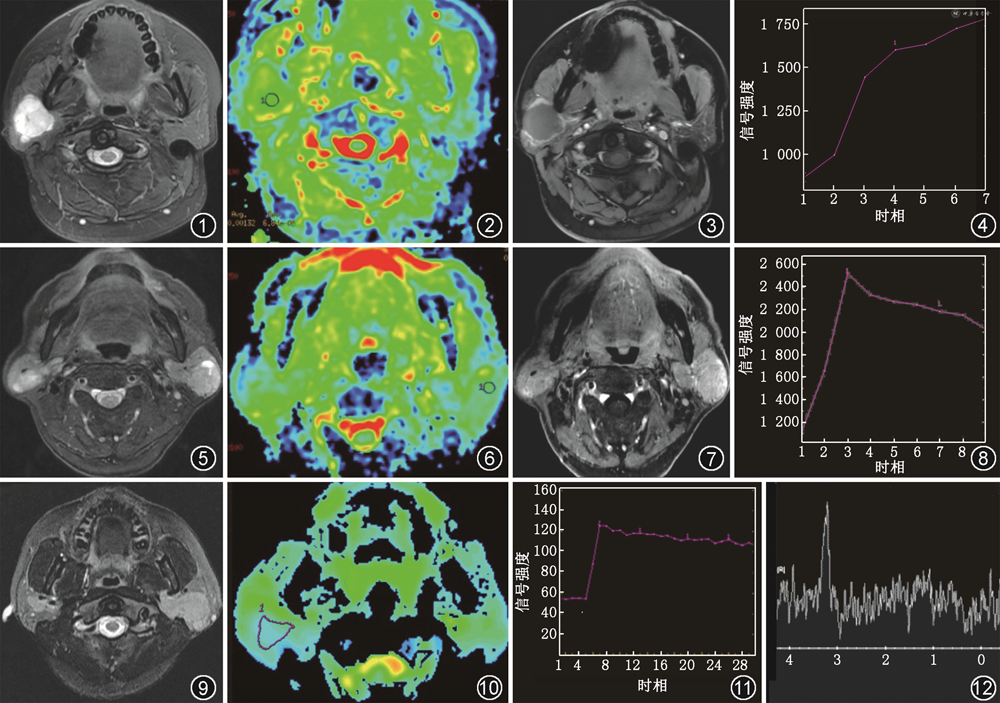

1.多形性腺瘤:在涎腺肿瘤中最常见,约占所有涎腺肿瘤的60%。发病年龄较为广泛,平均年龄为46岁,女性略多见。多形性腺瘤生长缓慢,主要表现为无痛性、孤立性软组织肿块,以腮腺浅叶多见,也可位于深叶。肿瘤多呈圆形或类圆形,分叶状,边界清晰,T2WI可见肿块周围弧形线样低信号包膜。较小的病变,CT一般呈密度均匀的软组织肿块;较大的病变,CT呈密度不均的软组织肿块,其内可见低密度液化坏死和囊变区,有时病灶内可见钙化。MRI上,T1WI多呈低或等信号,T2WI多为不均匀高信号(图1),其内部黏液样组织部分呈更高信号。DWI多呈扩散受限表现,ADC值为(1.43±0.26)×10-3 mm2/s(b值为0、1 000 s/mm2,图2)[5]。Merino等[10]提出ADC值>1.4×10-3 mm2/s高度提示多形性腺瘤。由于多形性腺瘤的肿瘤微血管密度低,且含软骨样间质,TIC多呈A型(持续型,图3,4)。Lam等[11]研究表明>90%的A型TIC肿瘤是多形性腺瘤。MRS上3.20 ppm处一般无明显升高的Cho峰。

2.腺淋巴瘤:多见于中老年男性,平均年龄为62岁。腺淋巴瘤与吸烟关系密切,吸烟者腺淋巴瘤的发病率是非吸烟者的8倍。临床多表现为无痛且有活动性的软组织肿块,位于腮腺浅叶下极,常为多中心性。肿块呈圆形或类圆形,直径2~4 cm,边界清晰,多见完整包膜。CT表现为均匀等密度结节,也可表现为低密度囊变伴壁结节。MRI上,T1WI呈等或低信号,T2WI稍高信号,可见更高信号囊变区(图5)。由于含高浓度黏液的囊样结构和淋巴样组织,DWI显示扩散受限,ADC值偏低,低于腮腺恶性肿瘤,ADC值为(0.86±0.13)×10-3 mm2/s(b值为0、1 000 s/mm2,图6)[5]。典型的腺淋巴瘤微血管密度高较高,TIC通常为B型(廓清型,图7,8)[12]。MRS一般无明显升高的Cho峰。

3.淋巴瘤:MALT淋巴瘤是最常见的唾液腺淋巴瘤。MALT淋巴瘤与干燥综合征有密切的关系,干燥综合征患者患淋巴瘤的概率显著增加,是正常人的5~20倍。腮腺淋巴瘤在CT及MRI上多表现为弥漫结节型,沿腮腺轮廓呈塑形生长,T1WI呈等信号,T2WI呈等或稍高信号(图9)。由于淋巴瘤细胞密集,核质比较高,DWI常表现为扩散明显受限,ADC值较低(图10)。文献表明,ADC值<0.669×10-3 mm2/s高度提示MALT淋巴瘤,其诊断的准确度为88.4%[9]。TIC常呈C型(平台型,图11)[13]。MRS可见Cho峰(图12)。Zhu等[9]研究发现Cho峰阳性诊断MALT淋巴瘤的灵敏度、特异度和准确度分别为80.0%、76.0%和77.7%。